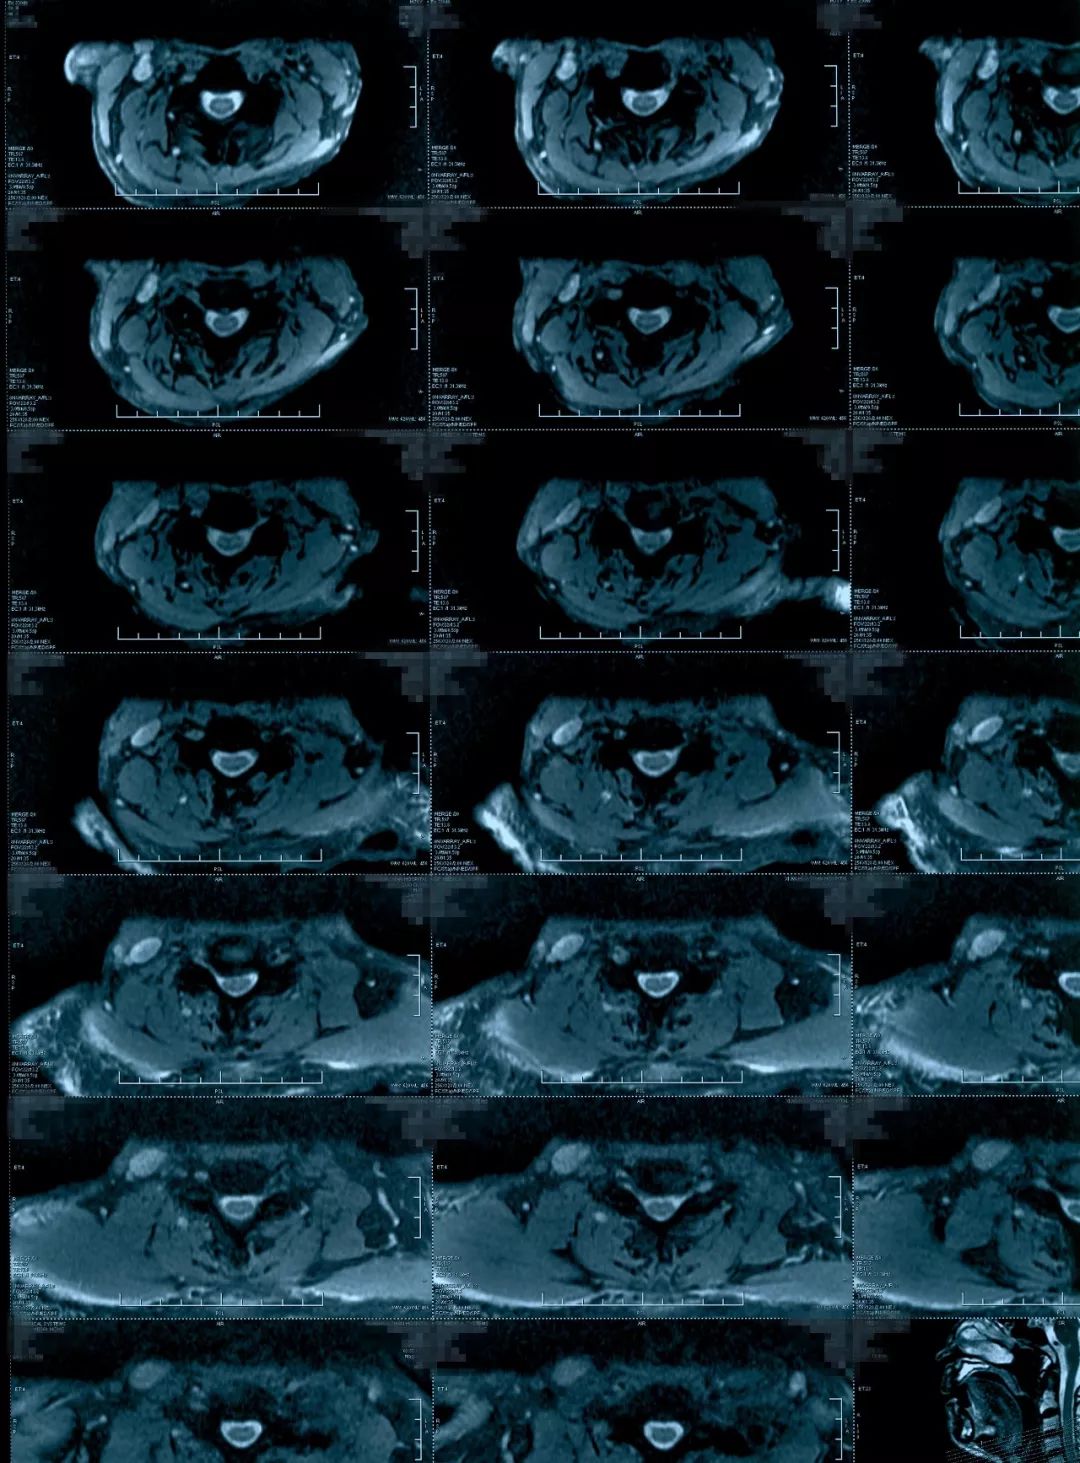

治疗后影像学资料

病人恢复得挺好,他的椎管是有一些容积减小,更主要是脊髓水肿造成的相对容积减小,如果对这种病人做椎管开大,也是能改善症状,但是毕竟病人做了一个手术,明确炎症之后做保守治疗能够恢复是更好的。明确了病因,病人本人是非常满意的,知道了自己是什么问题,最后得到了很好的治疗。